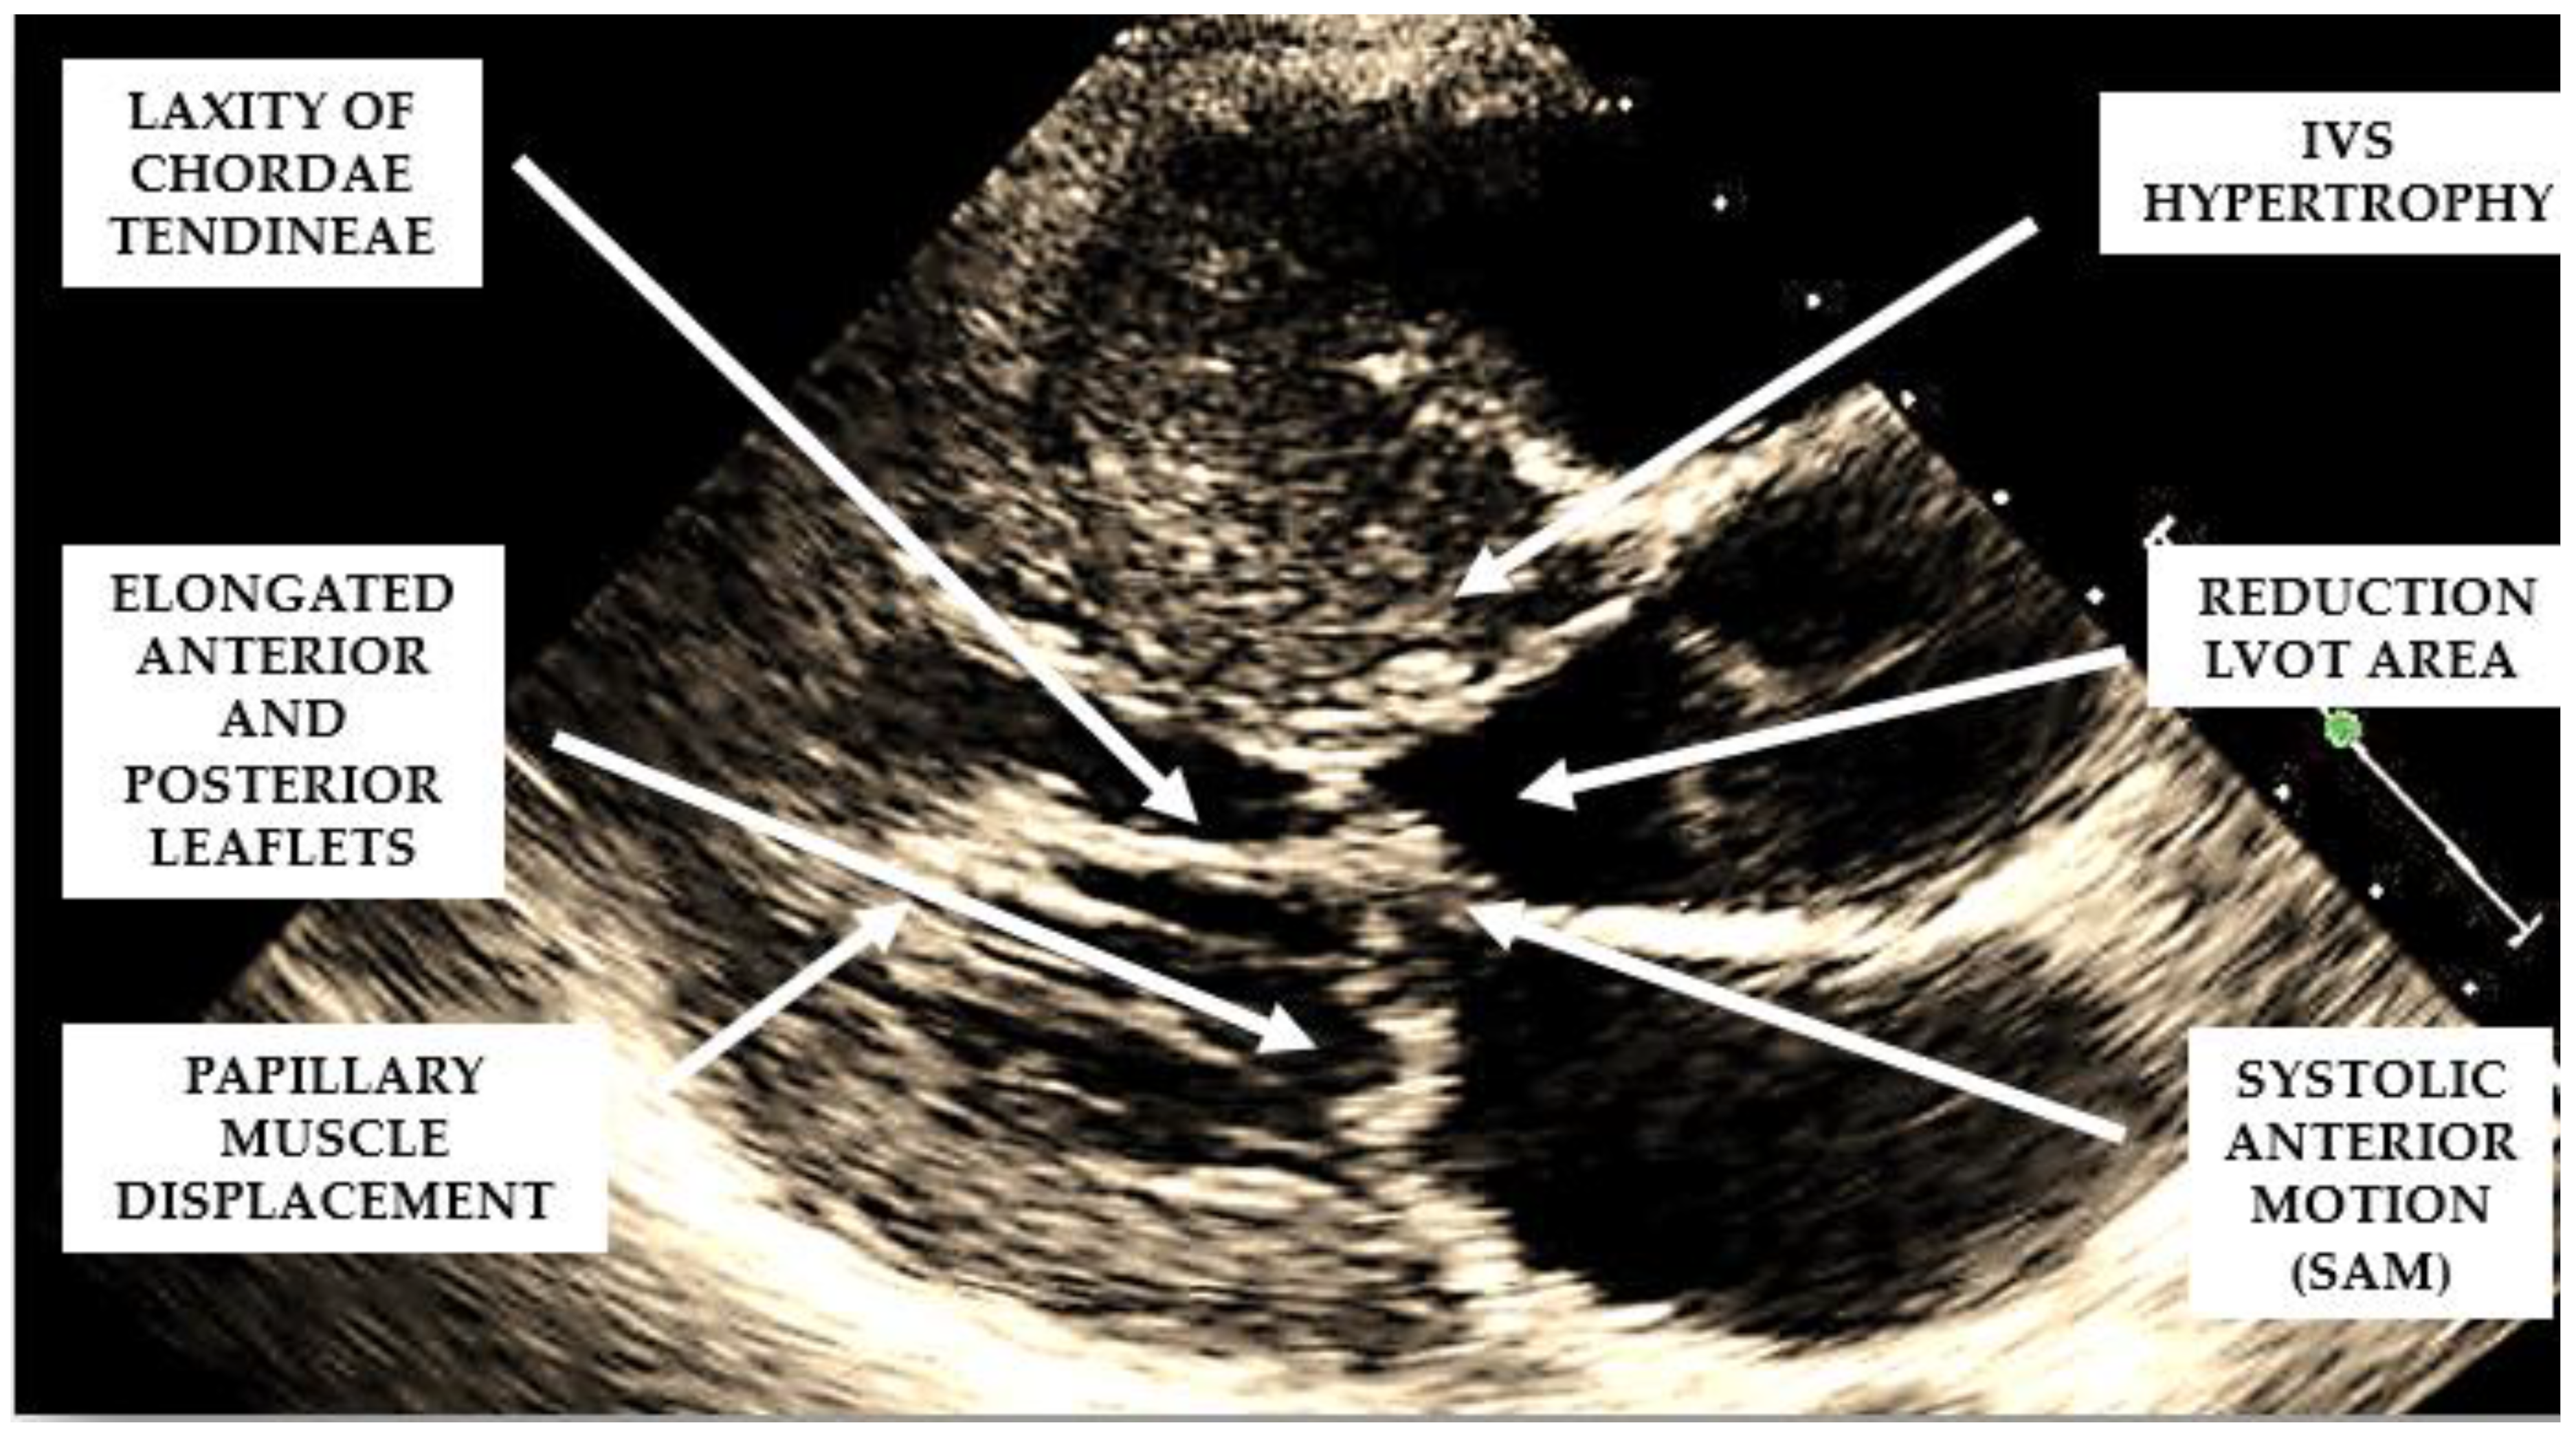

Several structural and functional abnormalities of the mitral valve may substantially contribute to LVOTO. The increase in length of the anterior and/or posterior mitral leaflets [10,11] (Figure 2), forward displacement of the anterior papillary muscle, and laxity of the mitral valve chords (Figure 2) have been implicated in the anterior displacement of the coaptation line and in abnormal leaflet coaptation, characterized by a posterior leaflet coapting the mid-portion of an anterior leaflet, leaving its distal portion unsupported. This part of the leaflet causes dynamic obstruction, via a combination of suction, caused by the Venturi effect of the rapid flow in LVOT, and a dragging mechanism, caused by blood pushing the leaflet towards the septum (Figure 2).

Figure 2.

Mechanisms involved in the generation of left ventricular outflow tract obstruction in patients with hypertrophic cardiomyopathy.

When evaluating the presence and severity of obstruction in HCM, a systematic assessment of all the components of the mitral valve apparatus via 2D echocardiography is required. This technique allows a visualization of the presence and distribution of LV hypertrophy, the presence of SAM, elongation of mitral valve leaflets, displacement of papillary muscles, laxity of tendon cords and LVOT diameter reduction (Figure 2). In addition, 2D echocardiography allows a diagnosis of MCO via the observation of a typical hourglass appearance of the LV due to systolic septal contact with the anterolateral wall, which induces sphincter-like cavity obliteration, creating two distinct (basal and apical) LV chambers (Figure 5). In addition, 2D echocardiography allows a visualization of the presence of an apical aneurysm and any thrombotic formation. In this setting, contrast echo may also be helpful for the correct diagnosis.